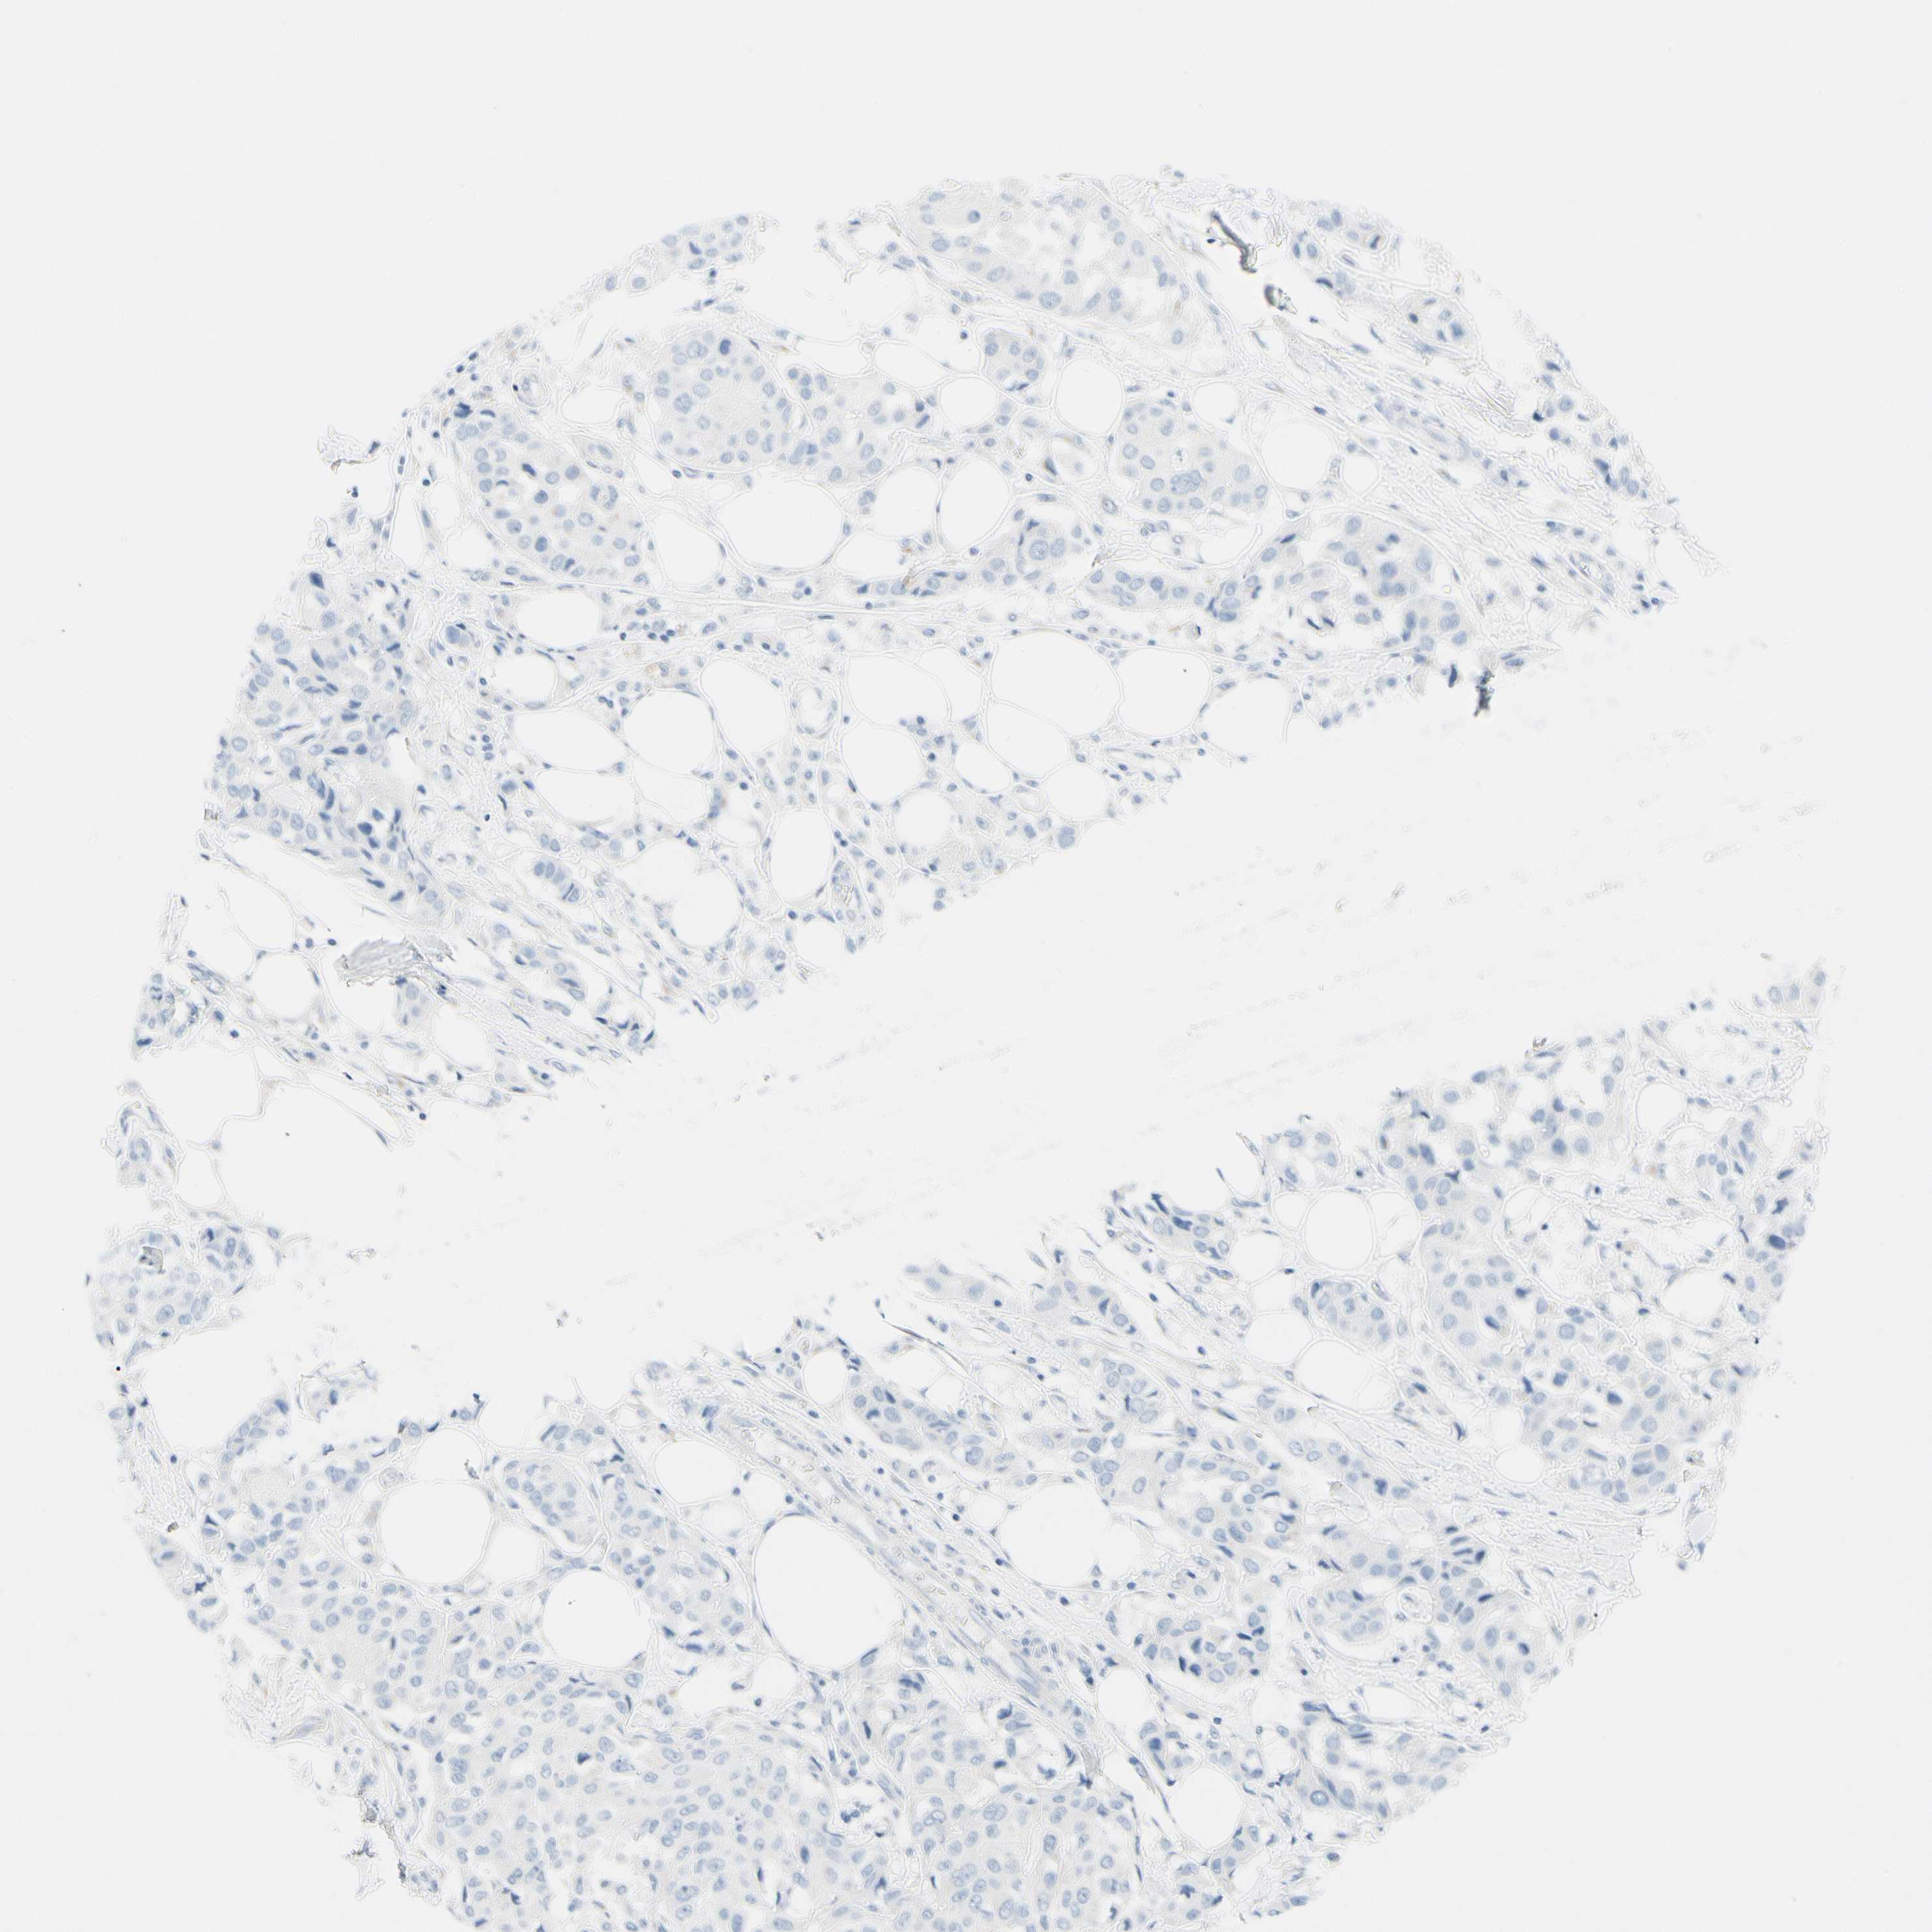

CANCER BREAST CANCER Show tissue menu

BRCA TCGA BRCA VALIDATION PROTEIN EXPRESSION